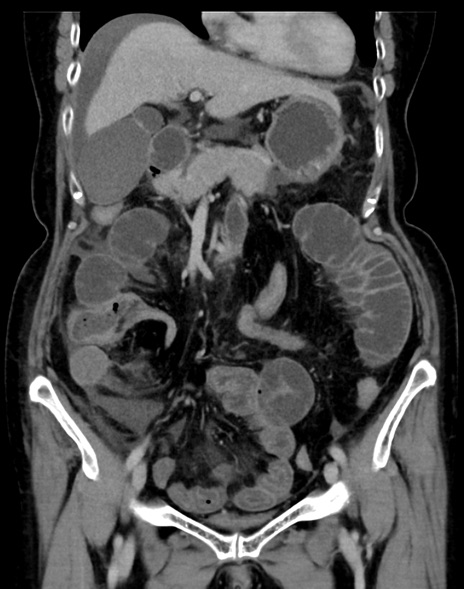

症例13 CT(冠状断像)1日半後